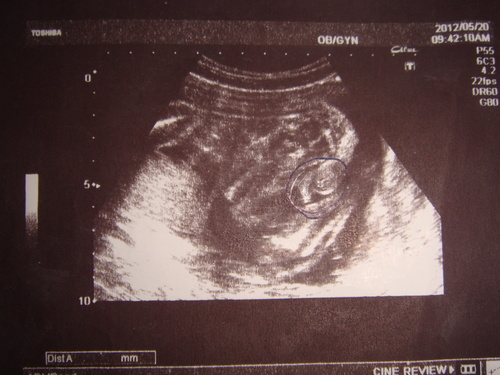

Беременность 22 недели мальчик

Беременность 22 недели мальчик 115 фото